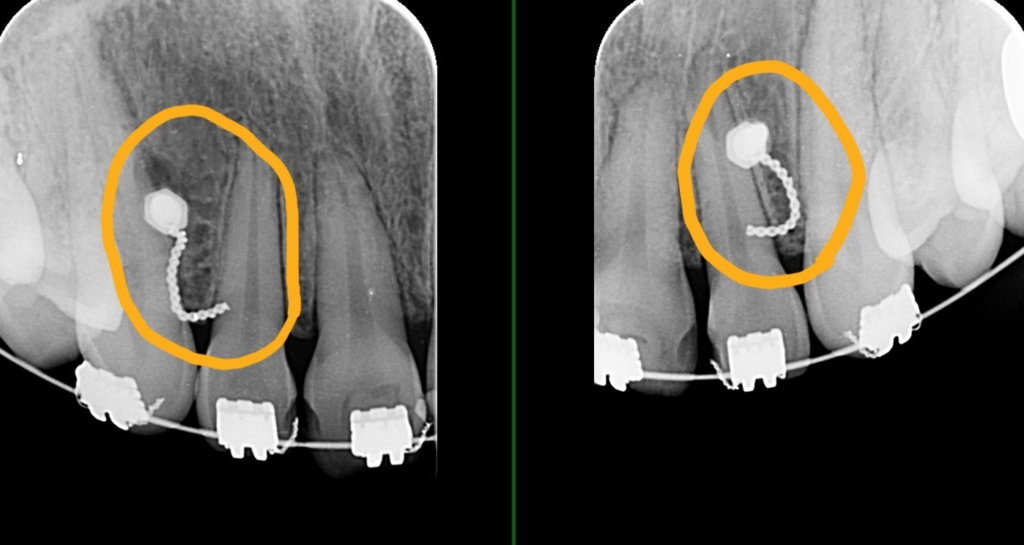

上の前歯が並んだので、ガミースマイルを改善させるために、前歯部にアンカースクリューを植立して準備を整えます。

そこからワイヤーを伸ばすことで「圧下」の力を加えることが出来るようにしました

ガミースマイルの改善が済んだ後、あらためて上の前歯を引っ込めるステップに入りました。

ガミースマイルの改善のために上顎前歯の圧下をした方でよくあるのが、この方のように前歯を引っ込めるステップで、スムーズに前歯が動いてくれない!という現象です。

前歯に限らず、「歯」というのは押し込まれるとそこで安定してしまい動きづらくなる・・・という特徴があります。 何の問題もなく動いてくれることもあるのですが、往々にして。この方のように時間がかかることを良く経験しています。